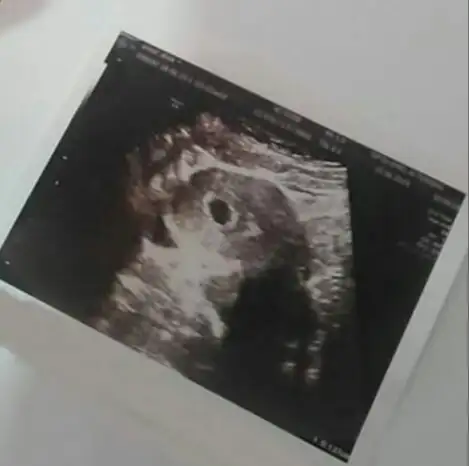

Canım dediğini yaptımCanım ultrason görüntüsünde sağa yakınsa kız sola yakınsa erkek derler bu bir ikincisi yüzük testi.yüzüğü ipe geçirilicek sırt üstü uzanıcaksın ,yüzüğü göbegıne dogru tutucaklar,yüzük ileti geri giderse erkek çember cıkarsa kız..benım yaptıklarımda bunlarr

Kız benimki tam ortada ya ultrasondaCanım ultrason görüntüsünde sağa yakınsa kız sola yakınsa erkek derler bu bir ikincisi yüzük testi.yüzüğü ipe geçirilicek sırt üstü uzanıcaksın ,yüzüğü göbegıne dogru tutucaklar,yüzük ileti geri giderse erkek çember cıkarsa kız..benım yaptıklarımda bunlarr

Canım ultrason böyle yüzük sallayınca da ileri geri hareket etti.Canım ultrason görüntüsünde sağa yakınsa kız sola yakınsa erkek derler bu bir ikincisi yüzük testi.yüzüğü ipe geçirilicek sırt üstü uzanıcaksın ,yüzüğü göbegıne dogru tutucaklar,yüzük ileti geri giderse erkek çember cıkarsa kız..benım yaptıklarımda bunlarr